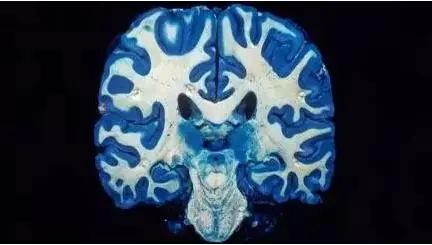

大脑灰质往往主导着人类的智力水平和学习能力,也包含感知能力、语言能力、肌肉控制能力、情绪控制能力和记忆功能。

简而言之,灰质减少预示着智力降低、认知迟缓、感觉迟钝以及语言、记忆发展缓慢,因此与正常发育的孩子比起来,大脑灰质少的孩子自然会呈现出智商的落后。

很多针对大脑灰质量的研究发现,在经过MRI大脑扫描之后,那些长期遭受虐待和忽视的孩子和青少年,大脑中灰质的量普遍少于家庭和谐温馨的孩子。

所以,作为一个习惯用棍棒来监督孩子学习的家长而言,也许正是因为你的习惯,从而导致孩子大脑损伤,学习成绩难上升。